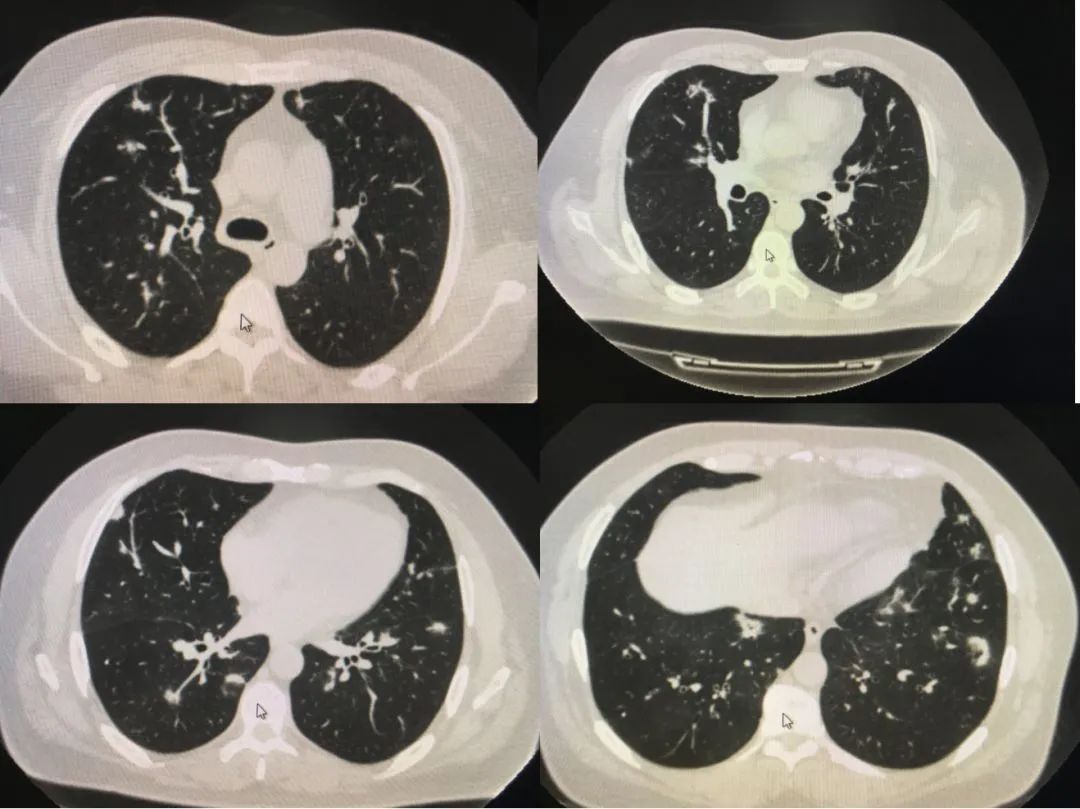

肺部小结节,肺癌片子

一起来看片~5分钟找到"肺部小结节"

肺癌片子

早期肺癌CT图

肺结节ct片图片图解

肺结节长什么样子图片

怎样看懂肺结节ct图片